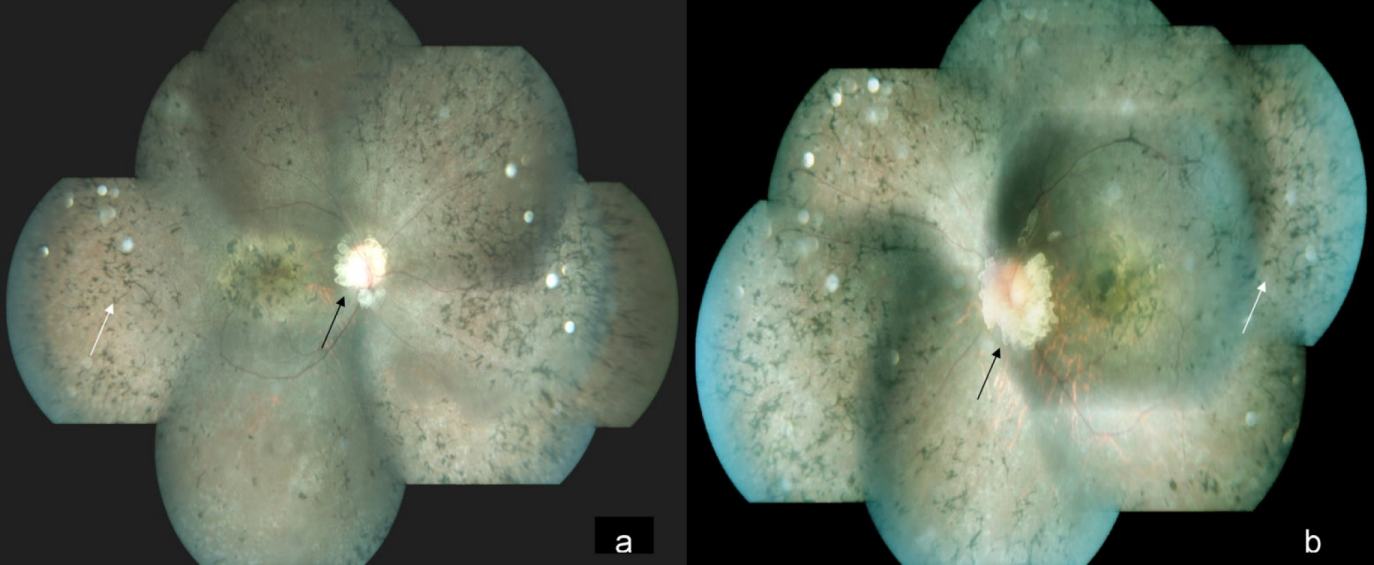

A 15-year-old male came to our hospital with gradual diminution of vision and night blindness in both eyes since 5 years. There was no family history of phakomatosis. Comprehensive examination did not reveal clinical features of phakomatosis. Best-corrected visual acuity was 20/1200 and 20/600 in right and left eye, respectively. Fundus examination of both eyes showed creamy white, semitranslucent, elevated lesion surrounding the optic disc along with attenuation of blood vessels and bony spicules in the mid-periphery (Figures 1a/b [Fig. 1]). Spectral domain optical coherence tomography showed moth-eaten optically empty spaces and hyperreflective dots (Figure 2b [Fig. 2] and Figure 3b) along with foveal thinning (Figure 2c [Fig. 2] and Figure 3c [Fig. 3]). Autofluorescence imaging of the optic nerve head (Figure 2a [Fig. 2] and Figure 3a [Fig. 3]) showed hyperautofluorescence. Multicolor image highlighted mulberry appearance of the lesion with green shift (Figure 4a [Fig. 4] and Figure 5a [Fig. 5]). In infrared reflectance (IR), margins of the lesion were better visualized (Figure 4b [Fig. 4] and Figure 5b [Fig. 5]). Green reflec-tance (GR) (Figure 4c [Fig. 4] and Figure 5c [Fig. 5]) and blue reflectance (BR) (Figure 4d [Fig. 4] and Figure 5d [Fig. 5]) showed multiple hyperreflective dots suggestive of calcification. A diagnosis of astrocytic hamartoma with RP was made.

Figure 1: Color fundus photograph of the right eye (a) and the left eye (b) showing a creamy white, semitranslucent, elevated lesion surrounding the optic disc (a and b) (black arrow) along with bony spicules (a and b) (white arrow) in the mid periphery